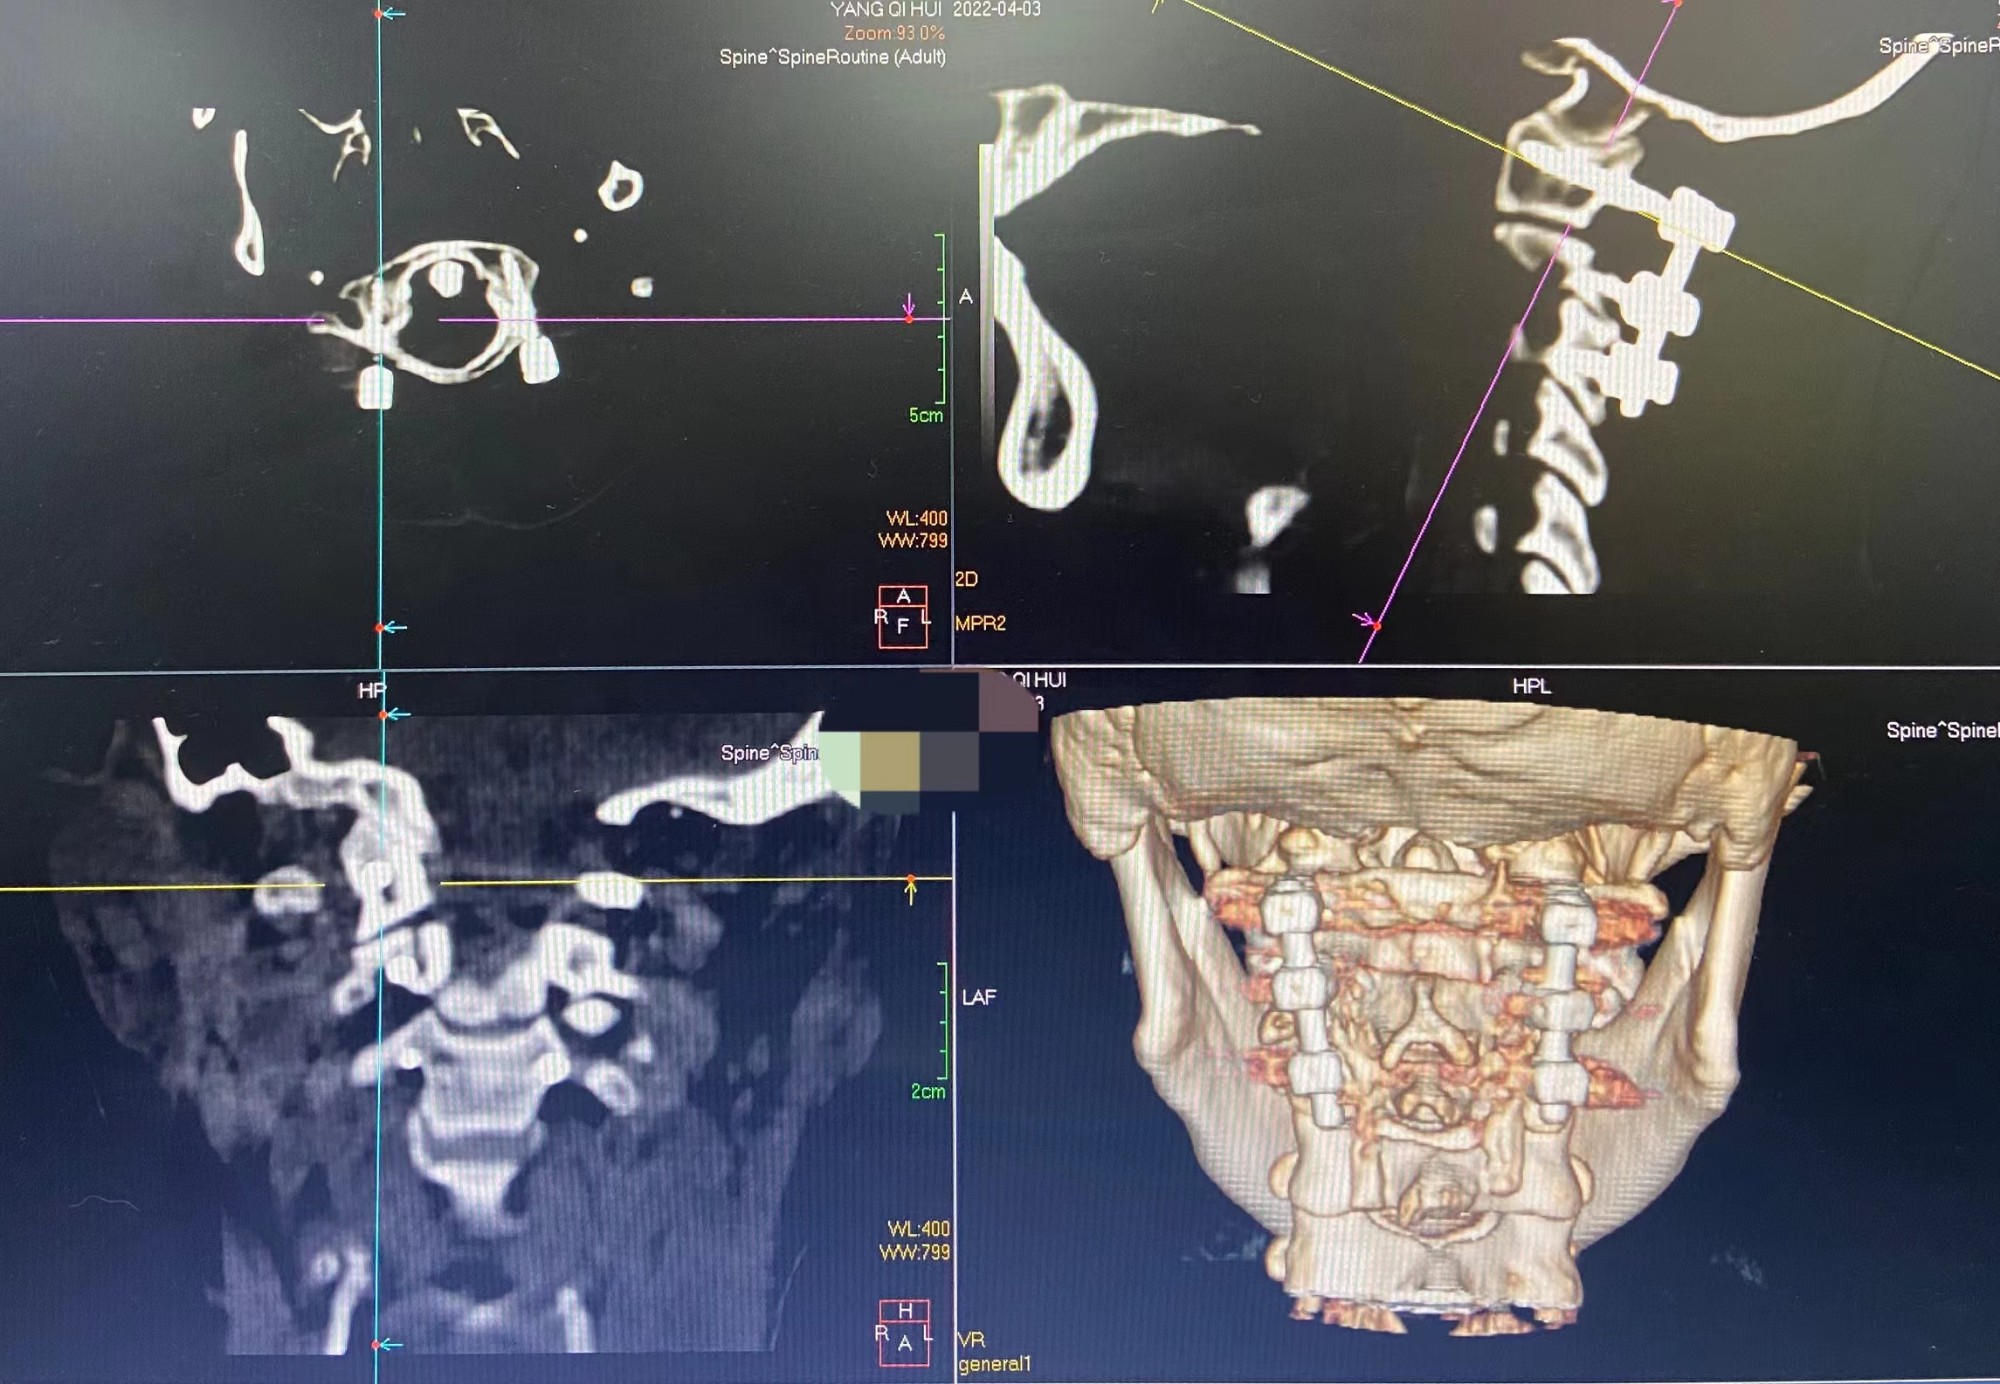

术后复查上颈椎CT显示螺钉位置良好